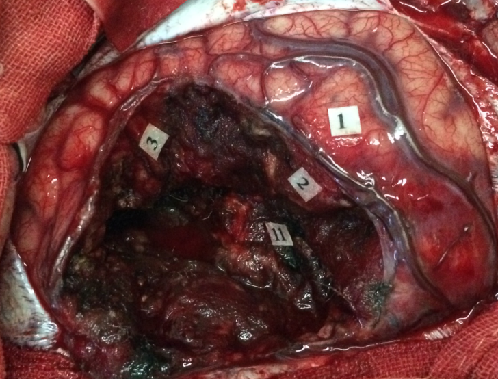

唤醒手术最大安全切除左中央区胶质瘤,术中照片:皮层电刺激(2.5mA)定位出患者感觉区感觉区皮质(标志点1小指,2拇指,3口角)和口角运动区(标志点4)以及数数中断并出现口角抽搐癫痫发作(标志点5),其中标志点5在肿瘤表面,肿瘤位于左中央前回腹侧。

保留功能区,尤其是标志点5,显微镜下电凝周边蛛网膜,切开至皮层下,在保留患者功能区的前提下,在持续监测患者运动和命名的前提下,先分离前方,至正常蛛网膜,再分离后方至正常蛛网膜。

电刺激为食指感觉(标志点9),下方切除标志点5下方的肿瘤,病人无明显失语,将标志点5切除,上方达一层蛛网膜,电刺激为手动(标志点7),深部切除过程病人语言含糊,电刺激为口角运动(标志点8)。